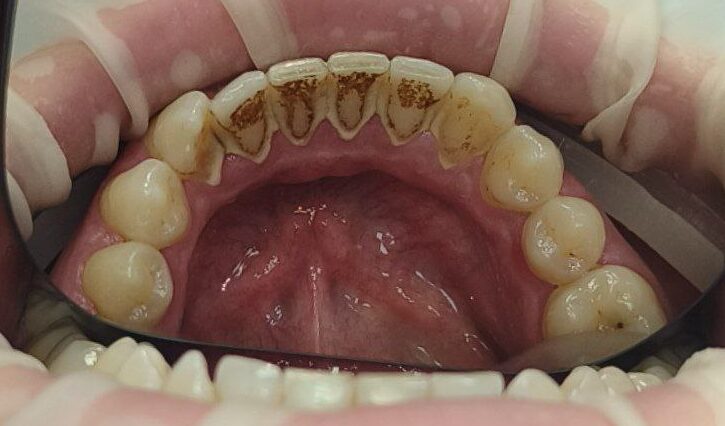

📌 ультразвукове видалення зубного каменю.

📌 аir-flow – м’яке очищення нальоту від кави, чаю та тютюну.